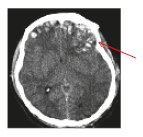

• Haematomas (Blood clots) refer to the collection of blood in one or several locations of the brain. Treatments for contusion and haematomas include observation for worsening of symptoms and removal of blood clots. Prognosis depends on the type, size, and eect of the injuries on the brain (Figure 3 and 4).

Bleeding from artery (Epidural haematoma)

Figure 3